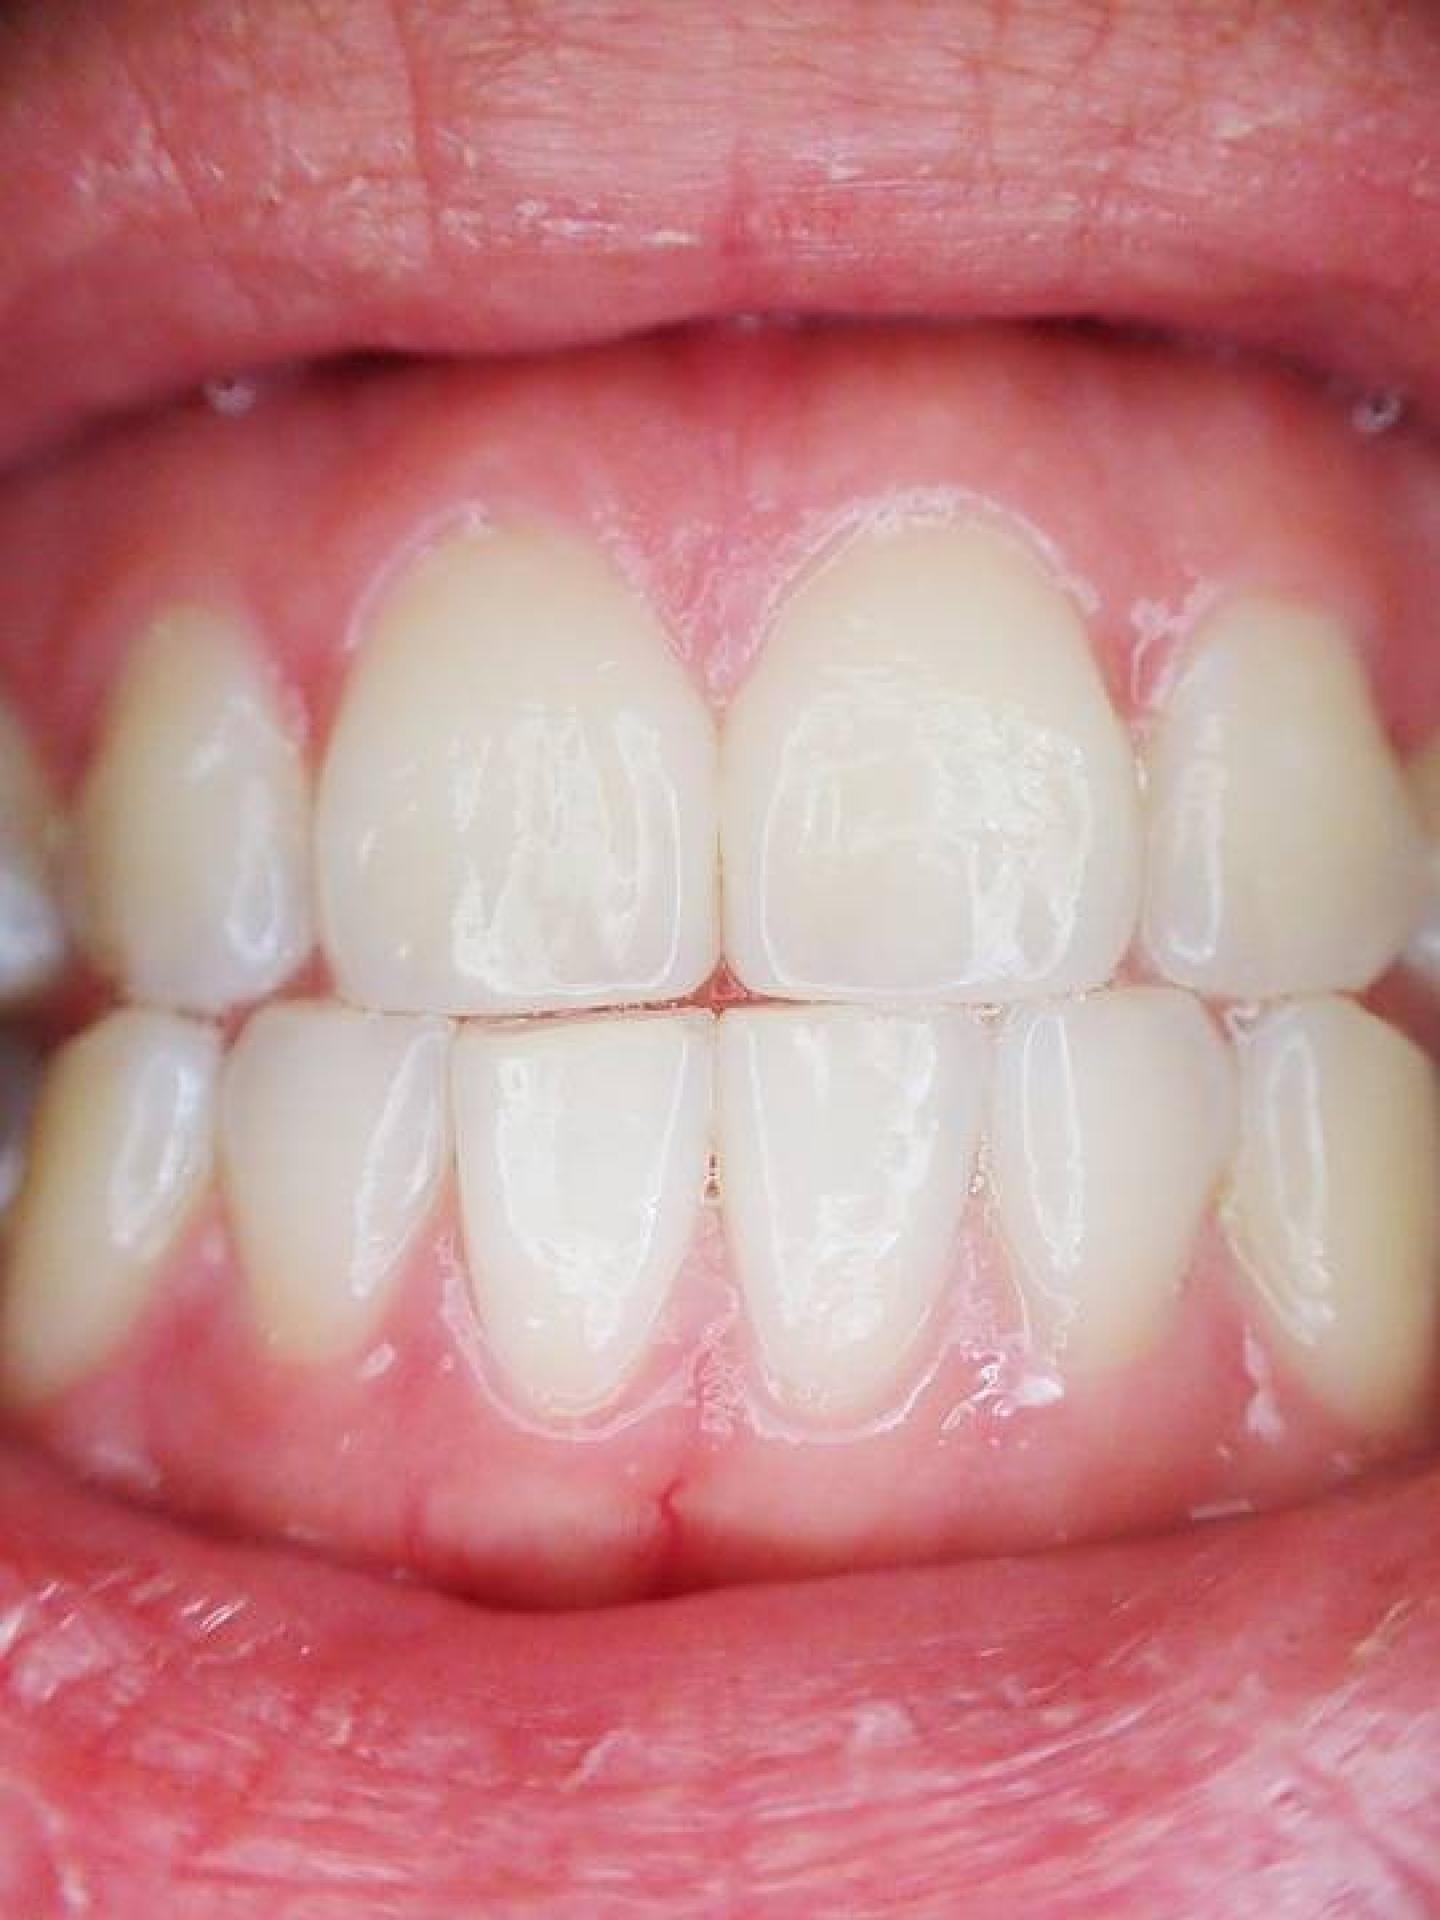

Praticien Invisalign® Marseille.Dr TOURROLIER Didier.

Plus de 4 millions de patients traités par la technique Invisalign® dans le monde .Découvrez cette nouvelle conception de l'orthodontie esthétique.

Le cabinet pratique l'orthodontie par gouttières transparentes pour l'adulte sur Marseille 13008 et ses alentours (Aubagne, Aix-en-Provence, Arles...), contactez-nous.